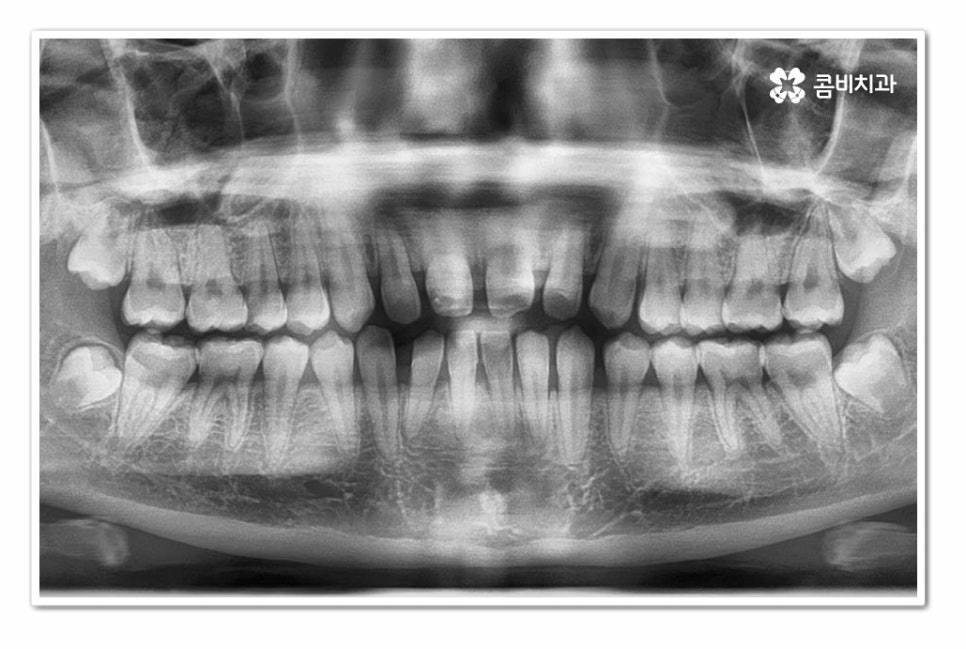

위 환자분의 경우 치아교정을 통해서 앞니 벌어짐 치료를 진행한 사례이며

치아의 이동 공간과 교합을 고려할 때 전체교정이 필요했던 사례라고 할 수 있어요.

위 환자분의 경우 윗니 만이 아니라 아랫니도 벌어져 있기 때문에

라미네이트와 같이 단기적으로 심미성을 고려한 치료보다는

치아교정을 통해 치아의 건강부터 교합, 심미성을 함께

개선할 수 있는 치료 계획을 세운 것이라 할 수 있어요.